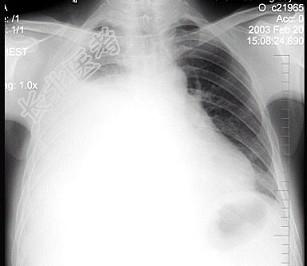

- 单项选择题男性患者,38岁, 感胸闷气逼2周,近来加剧, 不发热。X线检查如图,最佳诊断是 ( )

A、右侧肺不张

B、右侧胸膜肥厚

C、右侧大量胸腔积液

D、右侧中量胸腔积液

E、支气管扩张